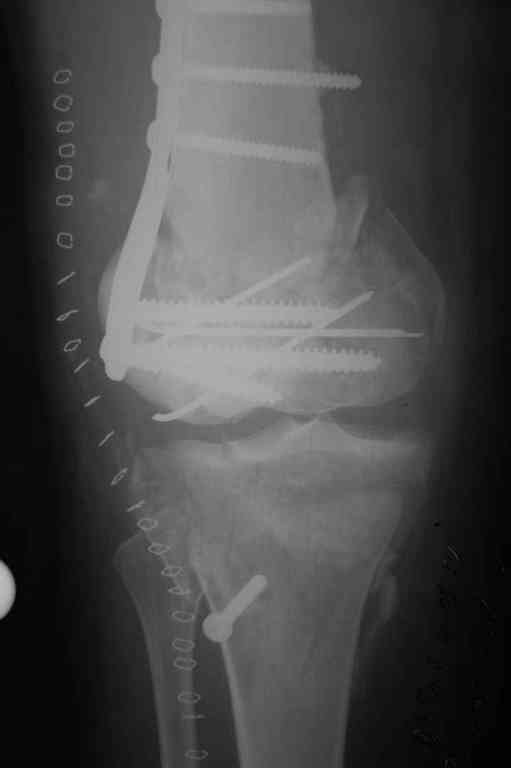

Re: Последствия открытого перелома дистального отдела бедра

Коллеги фиксатор Numelock II